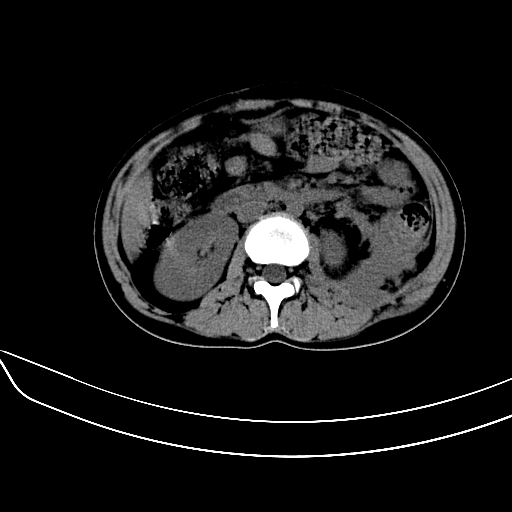

女,22岁,临床以糖尿病等病史入院,两年前有妊娠合并胰腺炎史,现有多饮、多尿、咳嗽、咳痰、左腰痛、发热等。因多种原因没做增强。

2、脾包膜下血肿、左侧腹膜后血肿(可能为特发性)。

考虑1: 糖尿病并发 肝脏脾脏梗塞不排除;少量腹水

脾梗塞,包膜下慢性血肿。肝脏低密度病灶不好说,脂肪肝算是一种可能。

肝、脾增大,内见多发低密度影,少量腹水,左侧肾周筋膜增厚,结合病人糖尿病史,有左腰痛、发热,考虑:糖尿病激发肝脾病变(梗塞?),左侧肾周感染,建议进一步检查。

真可惜,这么年轻就重病缠身,患者肝内,脾,肾,左下肺,左腰大肌均见病变,结合病史考虑感染可能性大。

左肾周感染,腰大肌脓肿,肝脾脓肿?不能增强,就来个mri。